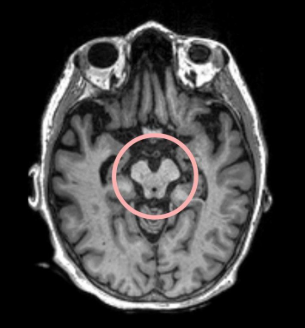

PSP is a neurological condition caused by the abnormal buildup of tau proteins in the brain. These proteins form tangles that damage nerve cells, particularly in areas like the brainstem, frontal lobes, cerebellum, and basal ganglia.

This degeneration affects movement, balance, vision, and cognition. While researchers are still working to understand the exact cause, most cases of PSP are not strongly linked to genetics.